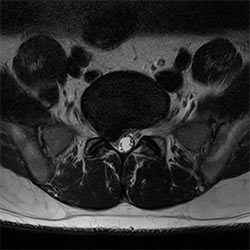

Cardiac